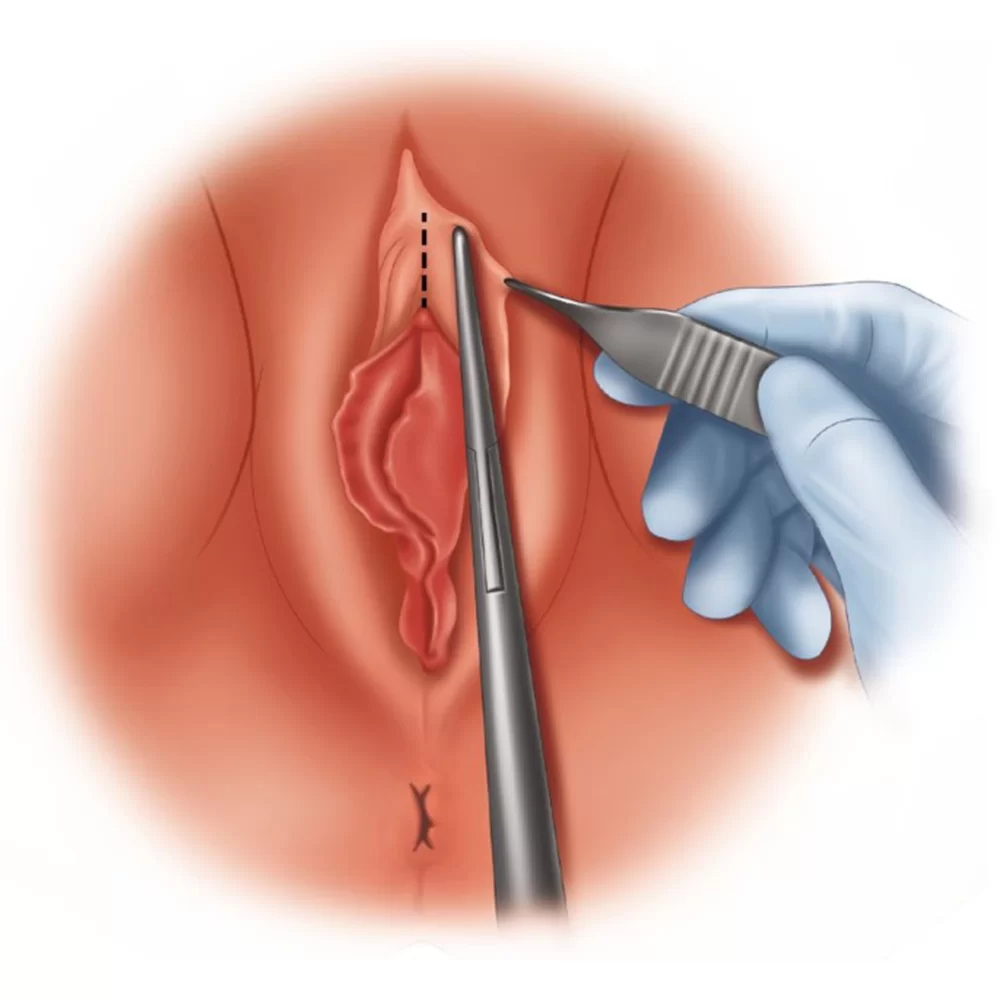

- فقدان مخاط دهانه رحم: درست قبل و در حین تخمک گذاری، معمولاً بیشترین ترشحات واژن به نام مخاط دهانه رحم را دارید که معمولا شبیه سفیده تخم مرغ خام است. اگر این ترشح را ندارید، ممکن است دچار عدم تخمک گذاری شده باشید.